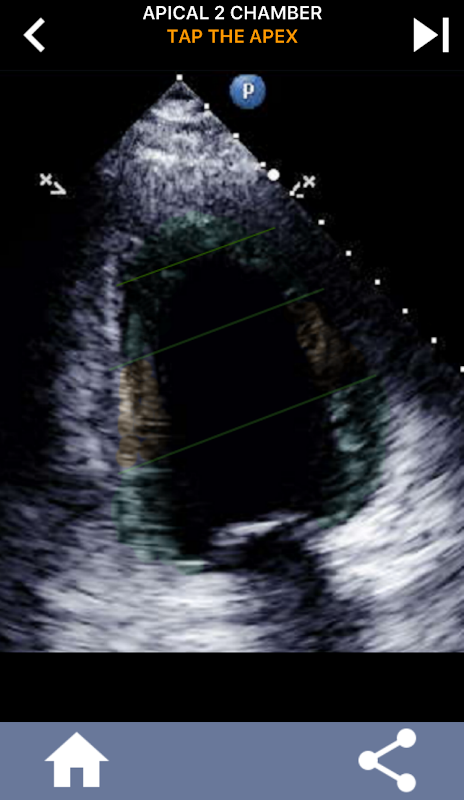

আল্ট্রাসাউন্ড ইকোকার্ডিওগ্রাফাররা আমেরিকান হার্ট অ্যাসোসিয়েশনের বাম ভেন্ট্রিকালের 17 টি সেগমেন্টে কার্ডিয়াক সেগমেন্টেশন শিখতে অপরিহার্য, যা অবস্থানের বর্ণনা দিতে চৌম্বকীয় অনুরণন ইমেজিং, কার্ডিয়াক পারমাণবিক পরীক্ষার ইত্যাদি অন্যান্য ইমেজিং পদ্ধতিগুলির দ্বারা ব্যাপকভাবে ব্যবহৃত হয়। প্রভাবিত সেগমেন্ট এবং ফাংশন। আপনার ইকোটি পড়ার সময় কতবার ব্যক্তি জিজ্ঞাসা করবে "আপনি কি দেখেছেন?" এবং প্রভাবিত এলাকা একটি সঠিক অবস্থান সঙ্গে উত্তর কি প্রত্যাশিত হয়।

এই অ্যাপ্লিকেশনটি এএএ খণ্ডিত মায়োকার্ডিয়াম দেখানো সমস্ত ইকো ভিউ ধারণ করে এবং আপনি সঠিক সেগমেন্টটি ট্যাপ করতে কুইজ করবে। আমি ব্যক্তিগতভাবে যে শিখতে দ্রুত / শিখতে বিষয় যখন আমার পুনরাবৃত্তিমূলক quizzing আমার জন্য ভাল কাজ করে। যদি আপনি আল্ট্রা / টিটিই অধ্যয়নরত আল্ট্রাসাউন্ড শিক্ষার্থী হন তবে আমি মনে করি এটি আপনার গবেষণার জন্য একটি চমৎকার পরিপূরক হবে।